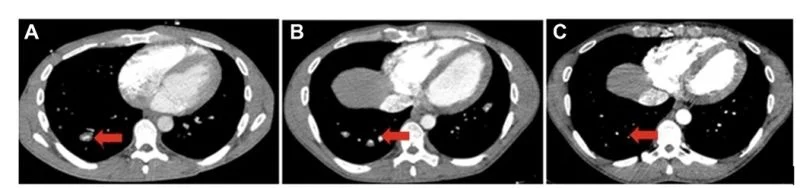

- CT scan of the chest with contrast revealed new, multiple dilated and aneurysmal pulmonary arteries and veins with in situ thrombosis A .